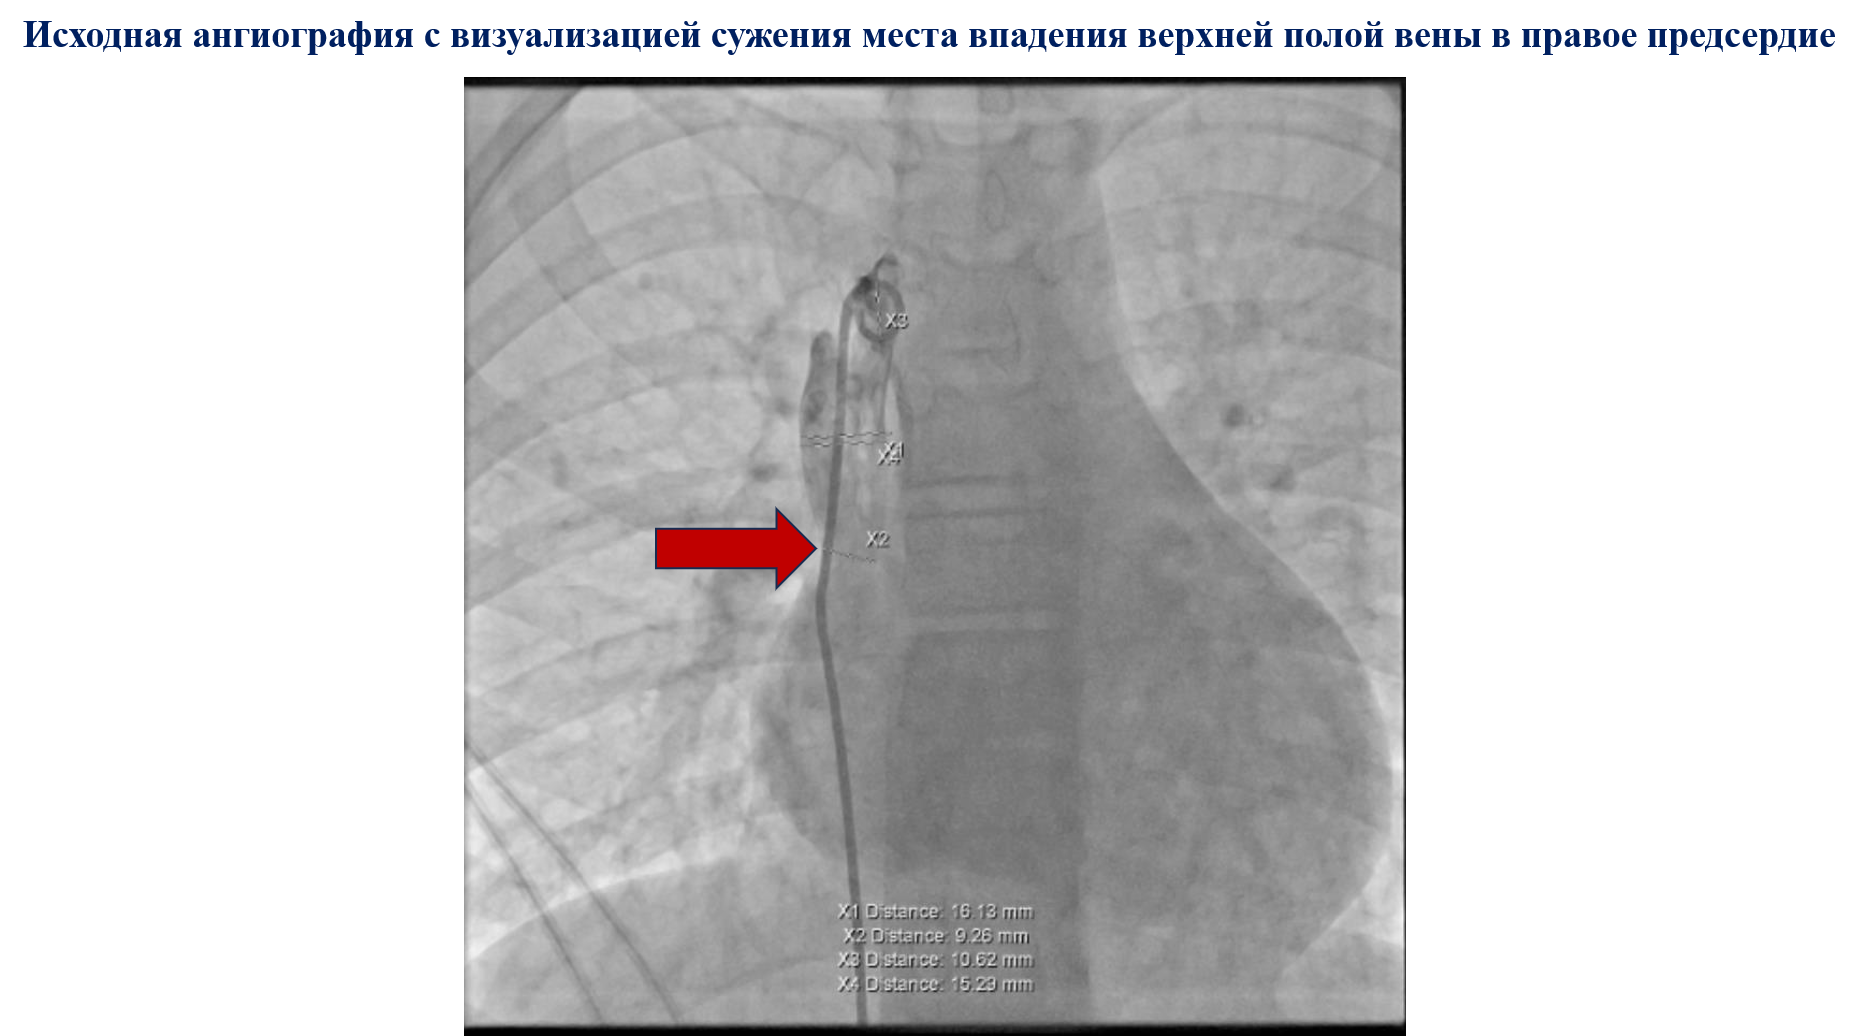

Впервые в Кузбассе выполнено стентирование сужения зоны верхней полой вены — правого предсердия. Пациент – мальчик 15 лет, у которого в анамнезе был редкий врожденный порок сердца, тотальный аномальный дренаж легочных вен, при котором легочные вены соединены с правым предсердием, вместо левого, как это должно быть при нормальной анатомии. Насыщенная кислородом кровь, таким образом, попадает не в левые, а в правые отделы сердца.

После операции в 2009 году ребенок регулярно наблюдался в клинике Научно-исследовательского института. В этом году он поступил с жалобами на отставание в физическом развитии, низкую толерантность к физическом нагрузкам. Его вес составляет 42 кг, что говорит о дефиците массы тела. Проведено обследование, в результате которого обнаружен стеноз верхней полой вены – правого предсердия. Рентгенохирурги приняли решение провести стентирование. Установлен стент в зоне реконструкции по поводу тотального аномального дренажа легочных вен. Стент AndraStent XL длиной 35 мм на баллоне диаметром 16 мм имеет потенциал дальнейшего расширения до 25 мм — по мере того, как ребенок будет расти, стент можно будет расширить, не производя замены. В результате операции врачи снизили средний градиент давления на стенозе с 9 до 1 мм рт ст. Значимым считается градиент по среднему давлению более 2 мм рт ст.